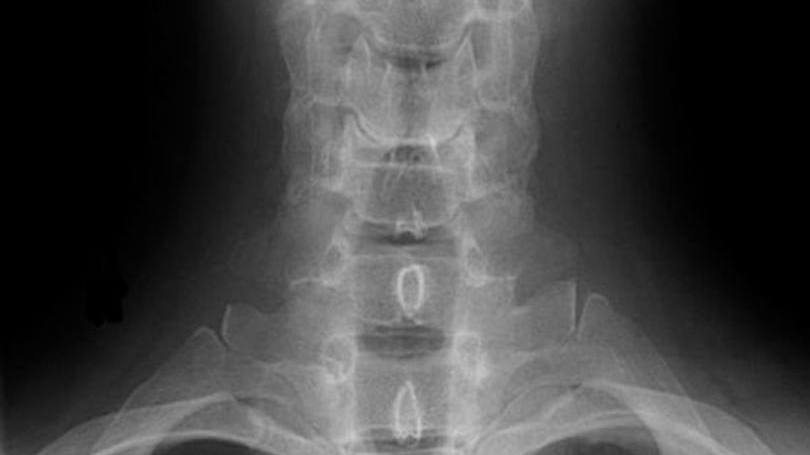

Além deste agravante, a má postura é outro problema que pode acarretar desde uma simples lombalgia (dor na região lombar da coluna) ou cervicalgia ( dor na região da coluna cervical) até casos mais graves de escoliose (encurvamento anormal da coluna vertebral) e hérnia de disco (lesão dos discos que compõem a coluna vertebral).

O fisioterapeuta Giuliano Martins, diretor regional da Associação Brasileira de Reabilitação de Coluna (ABRC) e diretor do ITC Vertebral Ribeirão, explica que o profissional que trabalha muito tempo no computador está sujeito a ficar com a tensão muscular aumentada na região do trapézio e também desenvolver dores cervicais e até de cabeça (cefaleia). O especialista dá dicas de prevenção. “Em um escritório é preciso estar atendo à postura durante todo o dia.